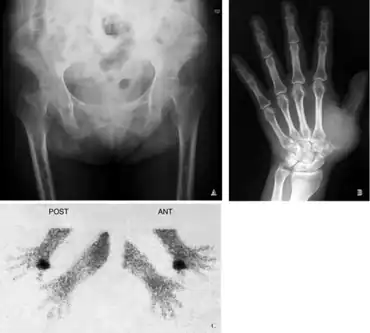

Radiographic characteristics

Radiological appearances include:

- Pseudofractures, also called Looser's zones.

- Protrusio acetabuli, a hip joint disorder

Additional imaging

In certain types of osteomalacia the following imaging techniques may be used:[18]

- MRI

- CT scan

- MR angiography

Furthermore, a technetium bone scan will show increased activity (also due to increased osteoblasts).